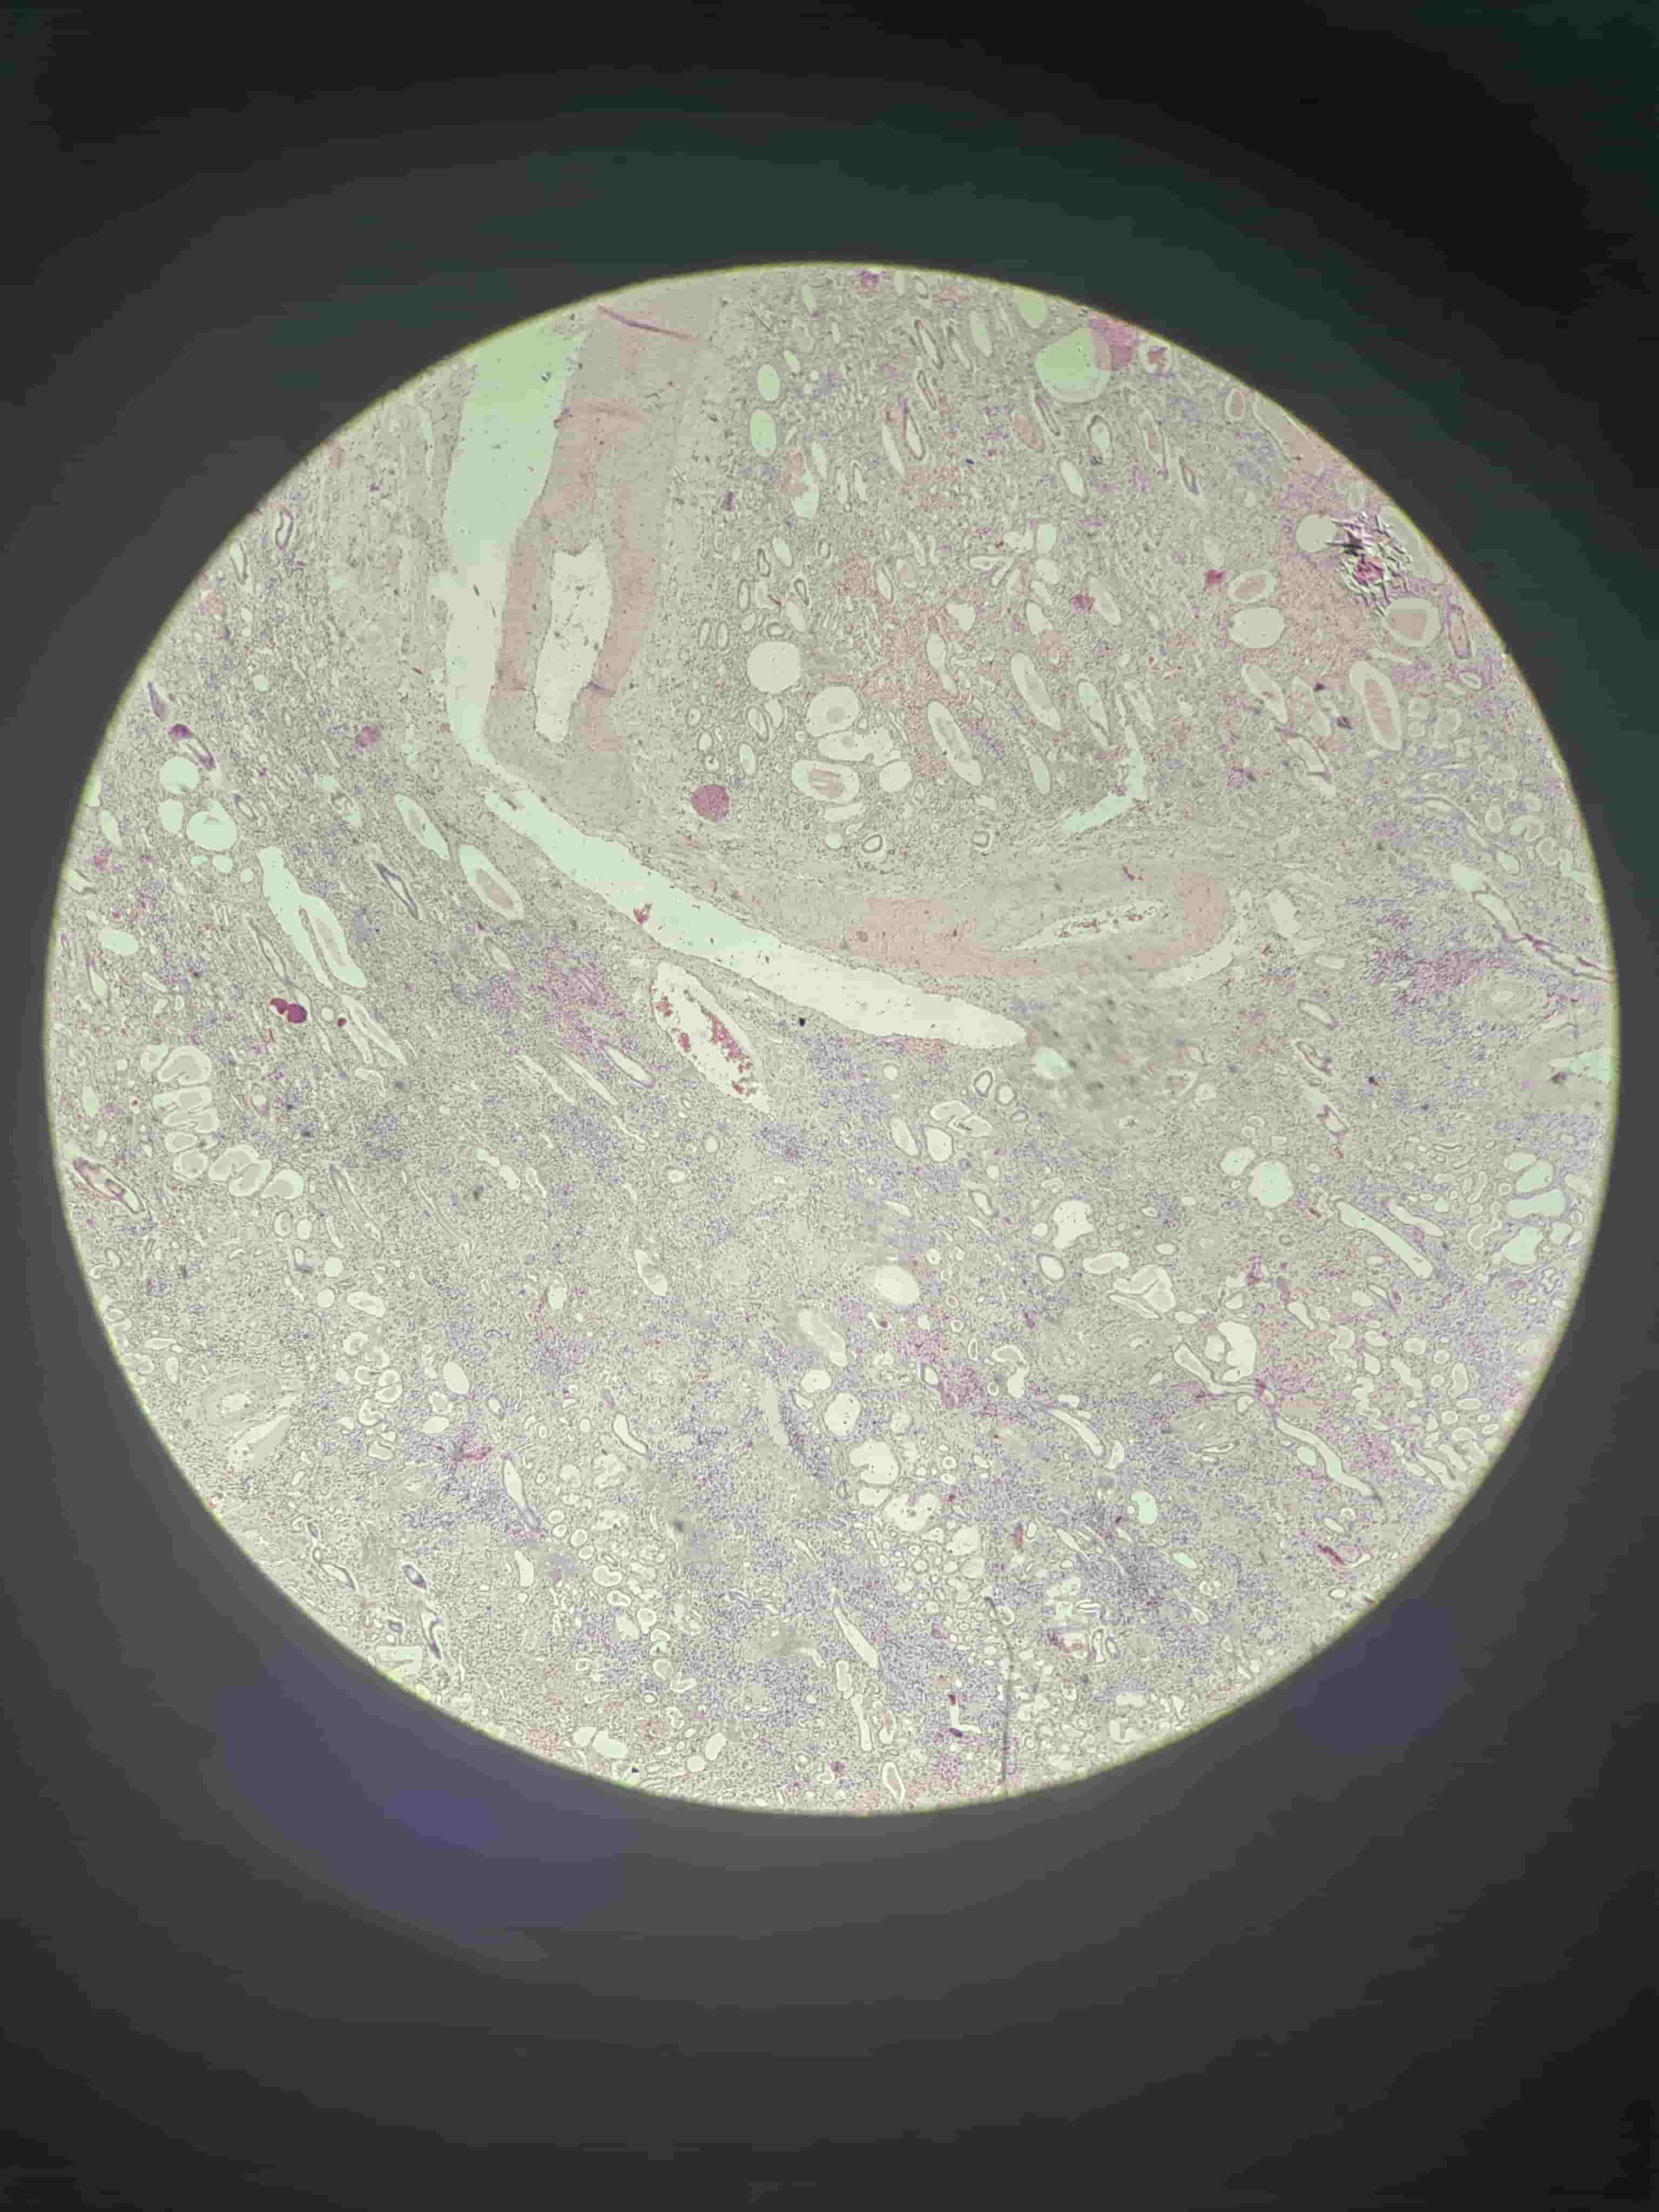

肉芽组织

- 毛细血管、成纤维细胞

- 炎细胞浸润